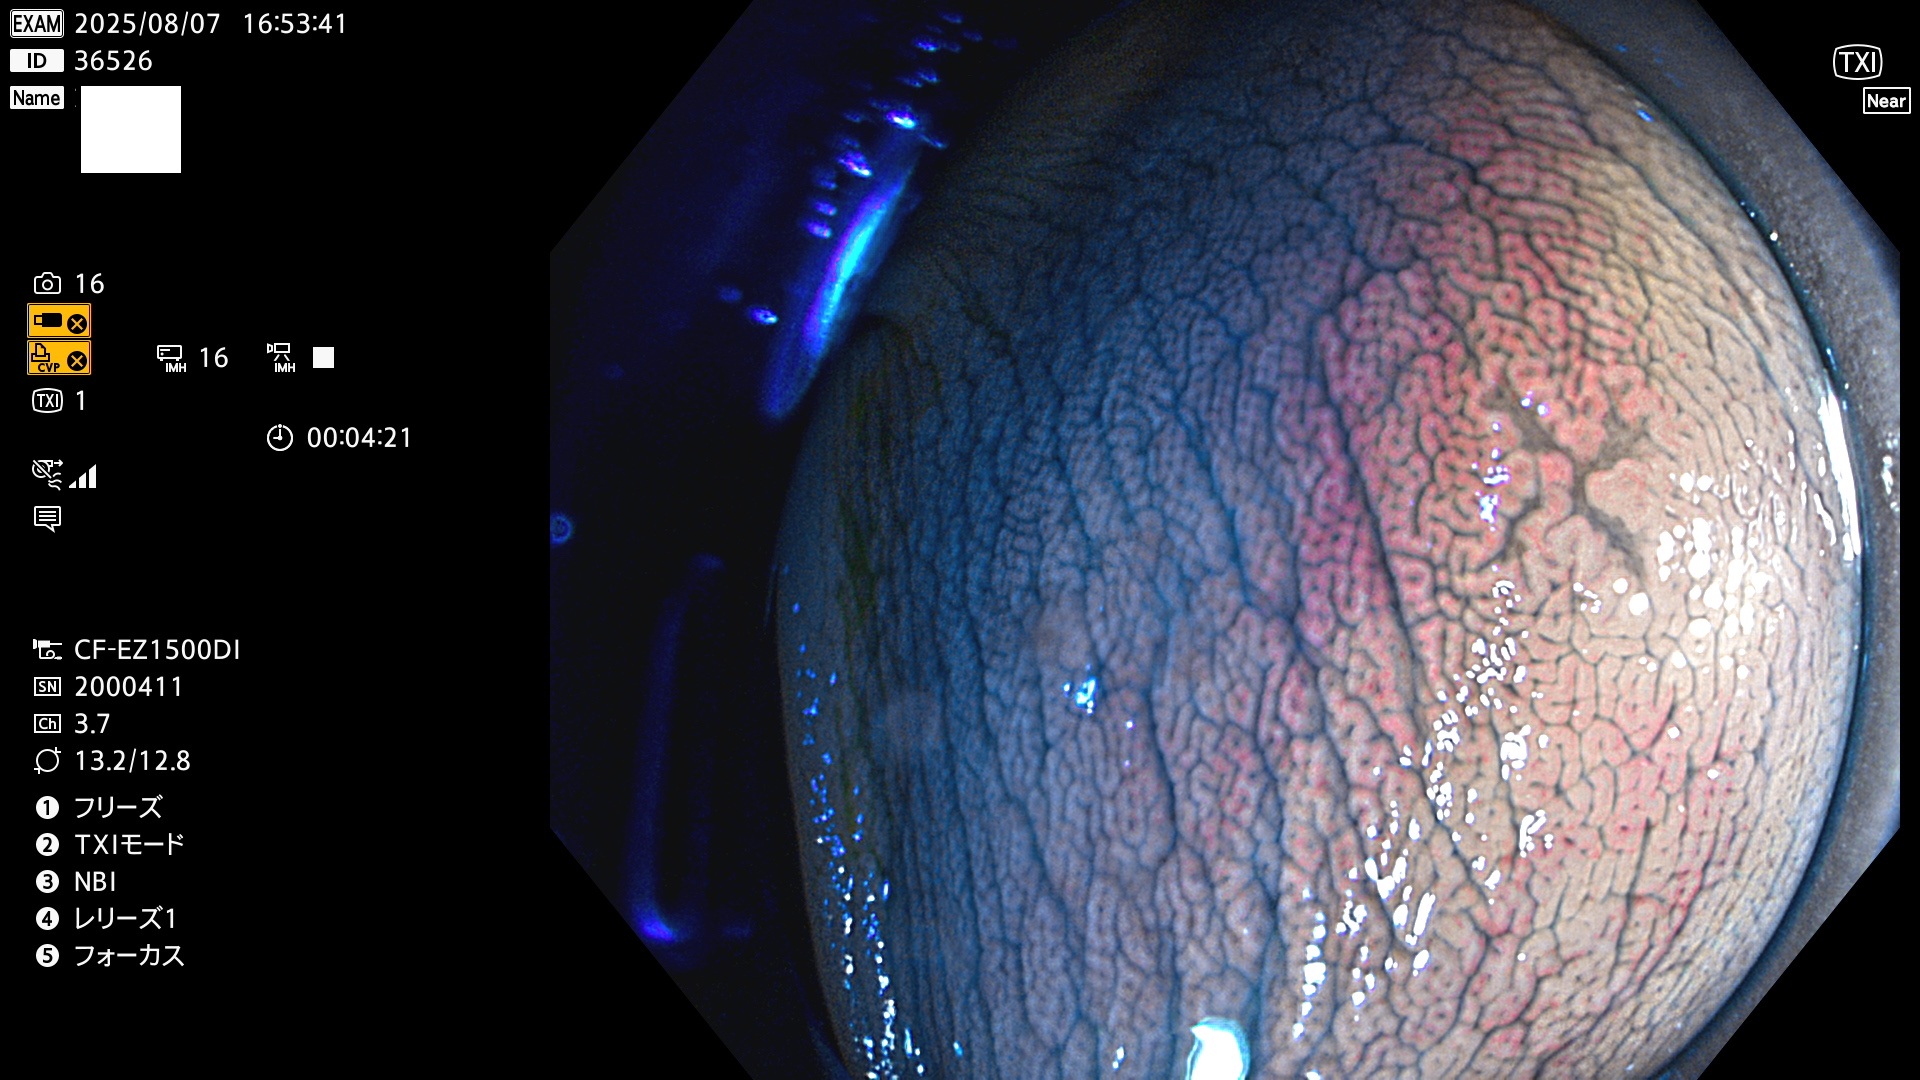

毎週の検査(木・金・土・日)に発見されたUbとUc型・腺腫を、その週の日曜の夜にUPし1週間、提示します。

写真公開の目的は「透明性・信憑性の担保」ですが、公開を希望されない方はメールで御連絡下さい。直ちに削除いたします。

2025年8月7日〜8月10日の4日間(35件)6個 (Uc_ADR=6個/35人=17%)